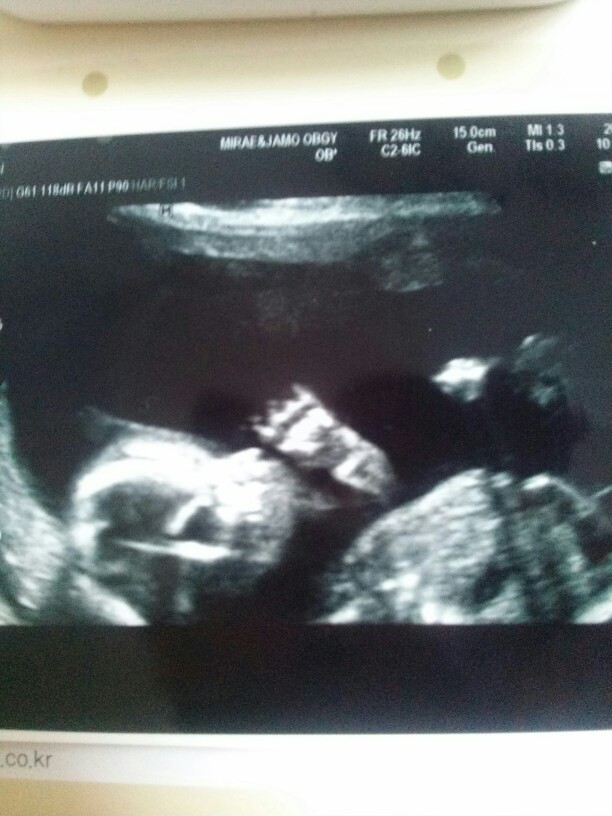

어제 울집 늦둥이 짱짱이 보러갔다왔어요 저렇게 열심히 손을 빨고 있더라구요 ㅎㅎㅎㅎ 다행히 주수에 맞춰 잘크고 있다고하네요 ㅎㅎㅎ

정말 늦동이시네요~~^^정말이쁨마니받겠어요 저두 늦동이 가질나이에 이제돌지난아기랑 뱃속에8갤애기품고있답니다 같은 임산부라그런지 애기춈파사진이 유난히 귀엽네요

어머낫~~포즈지대로잡고 찍었네영~ 요상태로 이쁘고 건강하게쑥쑥자라길~~~^^

딸랑구 원했는데 초음파에 미사일이 똬 ~하고 있네요 ㅎㅎㅇㅎ